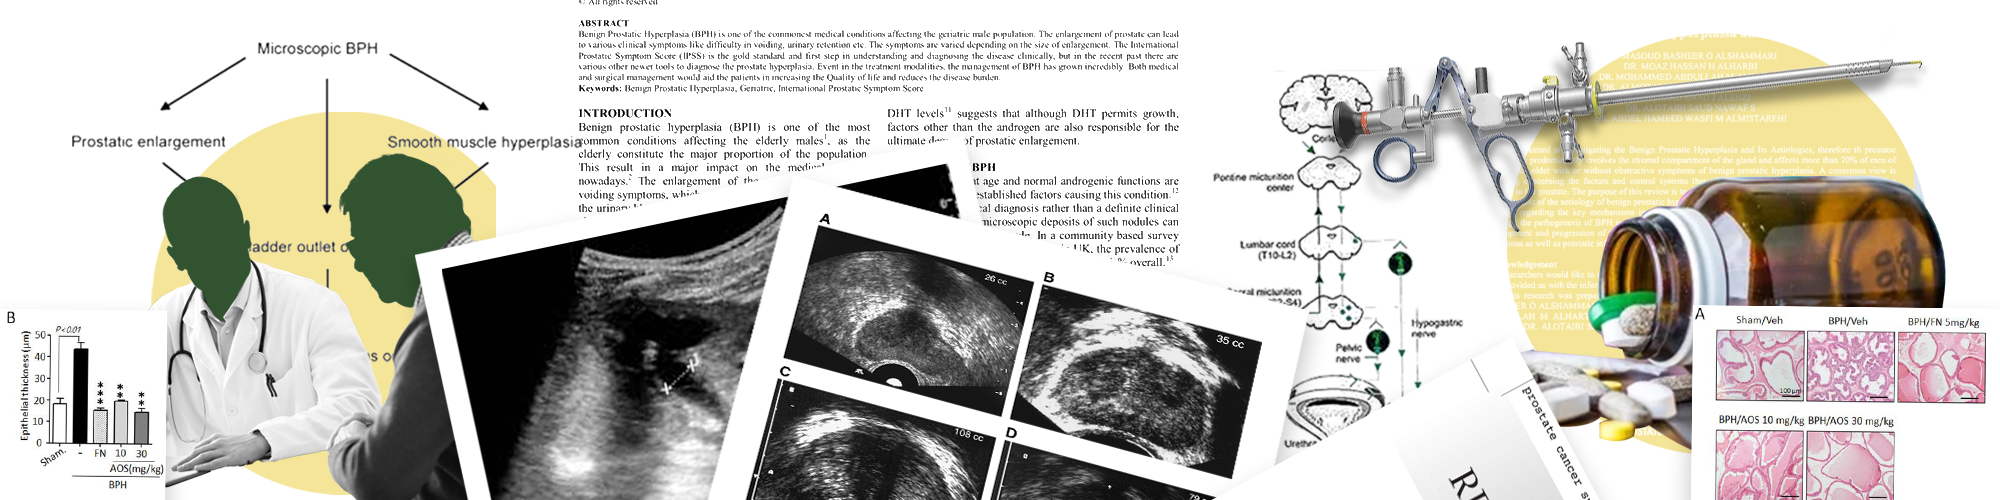

Benign Prostate Hypertrophy, also known as Benign Prostatic Hyperplasia, is a noncancerous enlargement of the prostate gland — a common condition as men age. The prostate surrounds the urethra, and its enlargement can block urine flow.

The Procedure

Treatment depends on severity:

Medications

• Alpha blockers (e.g., tamsulosin): relax prostate muscles to ease urine flow.

• 5-alpha reductase inhibitors (e.g., finasteride): shrink the prostate over time.

• Combination therapy: uses both for better results.

• Tadalafil: also FDA-approved for BPH.

Surgical Options

• TURP (Transurethral Resection of the Prostate): gold standard.

• Laser therapy (e.g., HoLEP)

• Prostatectomy for very large prostates

• Prostatic urethral lift (UroLift) or Rezūm water vapor therapy